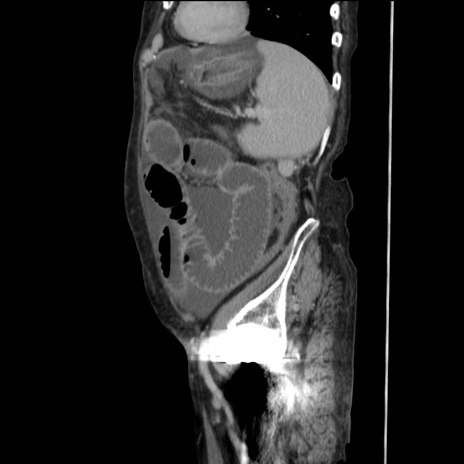

症例31(矢状断像)

【症例】80歳代 女性

【主訴】腹部膨満感

【現病歴】他院にて肝硬変にてフォロー中。1週間前から便秘、腹部膨満感、臍部腫瘤あり受診となる。

【既往歴】肝硬変

【身体所見】腹部膨隆あり、皮膚変化なし、疼痛なし。

【データ】WBC 4600、CRP 0.25